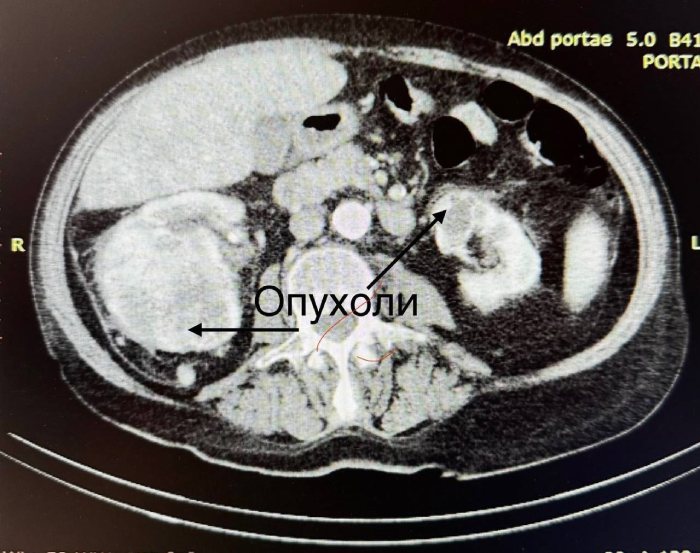

В Бурятском онкологическом диспансере провели операцию пожилому пациенту со сложным заболеванием. У него развился синхронный рак почек – онкопроцессы были и в левой, и правой почке.

Операция началась с лапароскопической резекции левой почки - аккуратно была удалена опухоль. Затем врачи приступили к удалению правой почки с опухолью, правого надпочечника и поражённых опухолью лимфатических узлов.